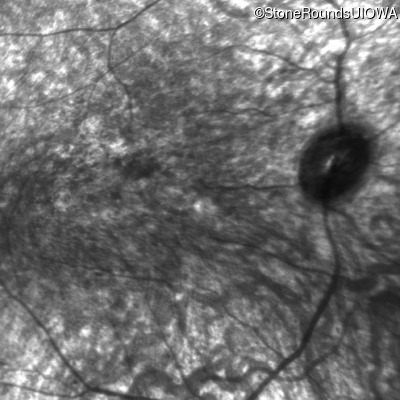

Infrared Fundus Photograph - Right - Hand Motion

Exemplar